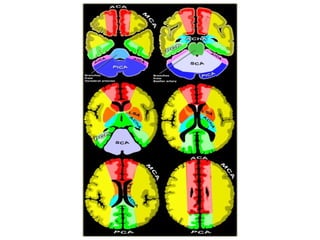

Vascular Territories

a) Vascular Anatomy

b) Cerebral Arterial Territory

c) Watershed Infarcts

d) Lacunar Infarcts

e) Posterior Reversible Encephalopathy

Syndrome (PRES)

f) Cerebral Venous Territory

g) Cerebral Venous Thrombosis

b) Cerebral Arterial Territory :

1-Posterior Inferior Cerebellar Artery

2-Superior Cerebellar Artery

3-Branches from vertebral and basilar artery

4-Anterior Choroidal artery

5-Lenticulostriate arteries

6-Anterior cerebral artery

7-Middle cerebral artery

8-Posterior cerebral artery